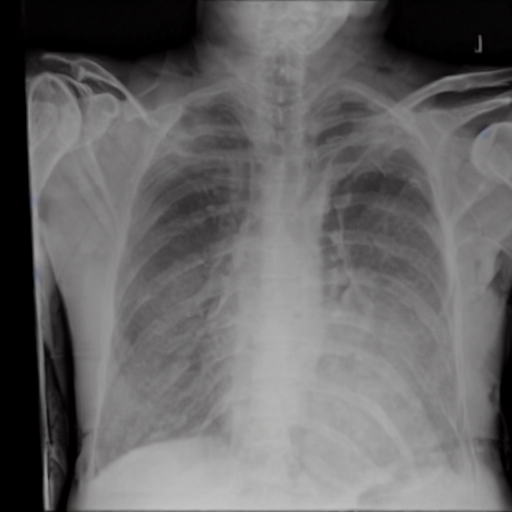

4.1 Qualitative Evaluation of Healthy Counterpart Generation

Example images from the disease COVID-19 Radiography Database and their generative healthy counterparts are given in figure 2. The images on the far left are instances of the lung opacity class from the real images in the dataset. The images in the middle column are examples of the generated healthy counterfactuals obtained via latent space diffusion, with RadBERT-guided textual-conditioning via a conditional prompt “normal chest x-ray”. A total of 75 diffusion inference steps are used with image conditioning strength=0.85 and guidance scale=7.5. (The former indicates the level of constraint on changes to the original input image and the latter is the weight given to the textual encoder conditioning in the generation of the image, ranging over [0,1] and [0,9], respectively).

Side-by-side inspection of the generated healthy counterfactuals (as per fig. 2) suggests that, as required, only minimal perturbation is made to the original image with respect to healthy pixels -i.e. localized image sites without structural medical defects. (In the top row, the medical structural defect in the original image is due to a lung opacity, and characterized via a relatively complex interaction between the imaging modality and subject manifesting as ‘gaps’ in the corresponding portions of the lung scan). The healthy/non-healthy discrepancy maps in all of these cases are obtained via masked subtraction of the original image from the generated image (the ground truth segmentation masks correspond to the broad area of interest –i.e. the complete lung). The generated healthy tissue is thus a subset of the mask and is shown in the final column of fig. 2 for the respective cases.

In the context of a VANT-GAN[20]-based approach, this highlighted material constitutes the diagnostic counterfactual visual attribution, i.e. the selection of material relevant to the diagnosis of the unhealthy condition. Healthy counterfactual generation was performed for the complete datasets in the three unhealthy classes, i.e Lung opacity, Viral Pneumonia and COVID, examples of which are given in fig. 3 for the three classes (all of the generated healthy counterfactuals from this experiment can be found on https://huggingface.co/ammaradeel/diffusionVA). Visual inspection indicates that the generated counterfactuals are, in general, visually plausible with minimal perturbation made to the unhealthy image overall. Moreover, the healthy counterpart generation does not appear to unnecessarily affect aspects of the images unrelated to the medical condition, the model selectively making changes to the unhealthy regions in a structurally plausible manner, e.g. generating missing portions of the lung without generating extraneous lung material where it would be expected to normally exist (e.g. in the abdominal cavity).